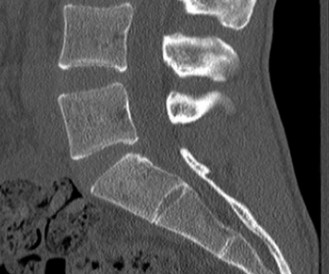

The correct answer is (A). As the case scenario strongly suggests an injury to the spine at the thoracolumbar junction, a CT scan of both the thoracic and lumbar regions is indicated. An MRI should not be the first imaging study obtained. Standing films should not be obtained in a trauma patient with a potentially unstable spine injury. A CT myelogram would only be obtained if an MRI was indicated but the patient had a contraindication to an MRI. Images of the above patient are shown inFigures 1–25 and 1–26. This injury is best characterized as which of the following? 1. Compression fracture

Figure 1–25

Figure 1–26

Discussion

The correct answer is (B). The images demonstrate an L1 vertebral body fracture with a small degree of kyphosis. There is comminution of the vertebral body with a posterior vertebral body fragment that is slightly retropulsed into the spinal canal. This separate posterior vertebral body fragment (which is noncontiguous with the pedicles) is the hallmark of a burst fracture. Compression fractures do not have any posterior vertebral body involvement. A Chance fracture, also known as a seat belt fracture or flexion–distraction injury, will exhibit distraction of the posterior elements through bone, bone-ligament, or purely ligament structures, with an axis of rotation somewhere within the anterior vertebral body or anterior to the vertebral body. A fracture dislocation exhibits translational deformities between the injured levels. While there appears to be a translational deformity on the sagittal CT, the vertebral bodies of the uninjured levels above and below are actually well aligned.